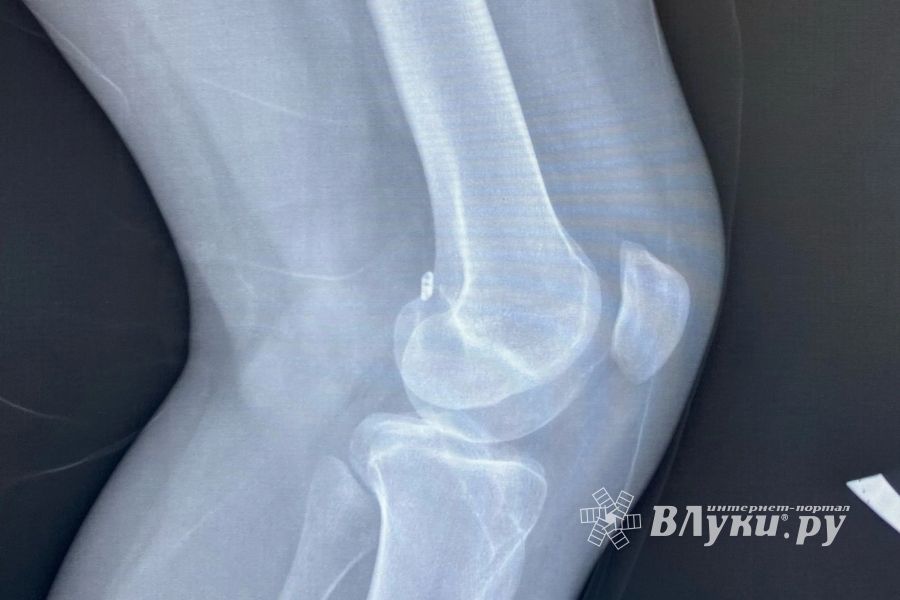

В Великих Луках остался только один рабочий аппарат для рентгенографии, и тот в инфекционной больнице на выезде из города, возмущаются в соцсетях горожане, пишет группа ВКонтакте «Граждане Великих Лук».

«Ребенок не может наступать на ногу, на руках нужно было нести, спасибо, что у родителей есть автомобиль и нас возили. А что у тех у кого нет авто, ждать час 15 маршрутку или 3 автобус, час обратно? При том что врач принимает всего 1 час. Не у всех есть возможность ехать на такси туда и обратно. Но не всё так просто, я еще и должна на телефон делать фото с монитора с результатами исследования и показать фото врачу! Неужели между учреждениями нет ни какой связи, чтобы пересылать друг другу данные? В поликлинике №1 тоже не работает аппарат не один месяц. Хорошо в железке можно сделать, но опять же не совсем дешёвое удовольствие. Вот почему так?», - написала одна из пострадавших от ситуации местная жительница.

«Рентген-аппарат в детской поликлинике и детской больнице города Великие Луки в настоящее время находится на техническом обслуживании. Поставщик медицинского оборудования производит замену комплектующих и устраняет неисправности. Для пациентов, нуждающихся в рентгенологическом исследовании, администрацией медицинской организации организована временная маршрутизация пациентов в инфекционную больницу.